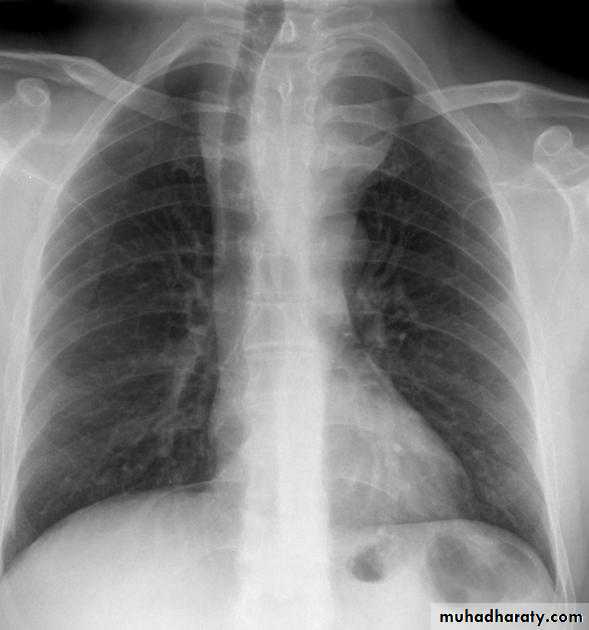

Pleural effusion

50.pleural effusion

51.pleural effusion .